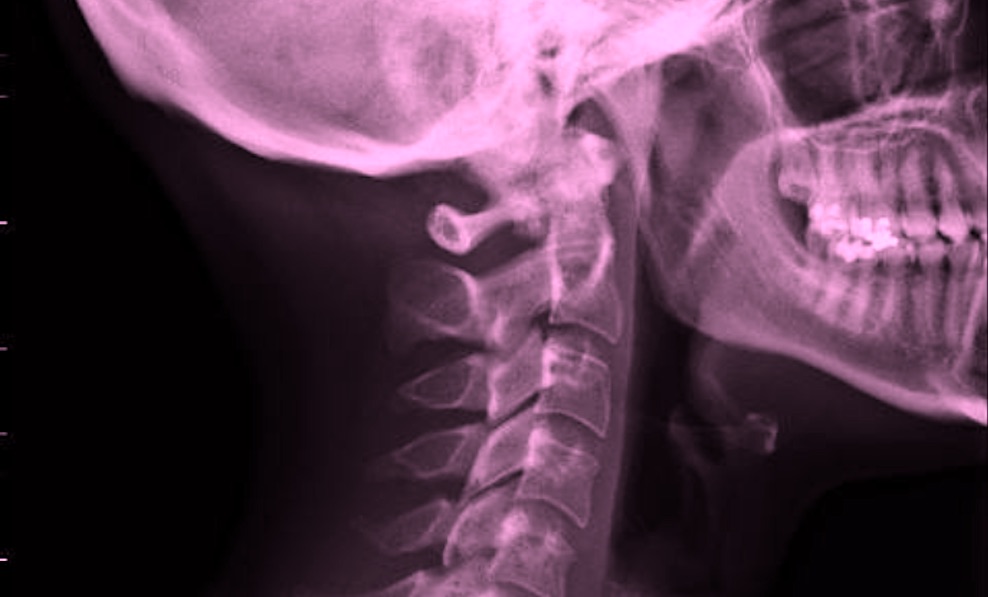

The electronic device is planned to be the size and flexibility of a small Band-Aid and will use high-resolution ultrasound technology to help doctors monitor and treat the changes in blood flow and prevent tissue death that occurs immediately after a traumatic injury to the spinal cord.

The new DARPA program combines neurotechnology, artificial intelligence, and biological sensors, to promote healing at the wound site and interfacing with the nervous system at points around the body o restore natural functions such as breathing, bowel and bladder control, movement, touch, and proprioception that can be lost when the spinal cord is damaged.